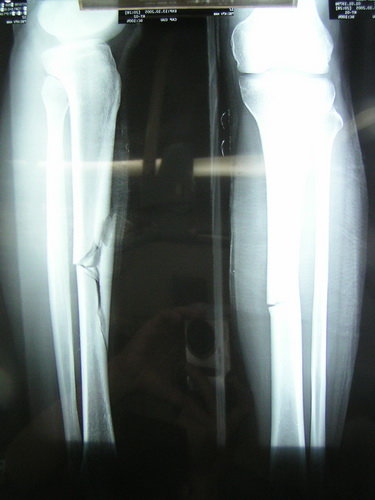

| Hình X-quang xương chân gãy nát. Ảnh Nam Anh |

| Xương gãy trên phim |